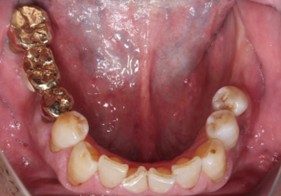

70代 女性

治療前

治療後

治療後- リスク・副作用

- 術後疼痛、歯肉腫脹

- 治療の費用

- 合計¥587,000(税込)

【内訳】

インプラント(1本)¥440,000

その他費用¥147,000

(薬・注射・レントゲン・CT・データ分析・サージカルステント・血液検査) - 年齢/性別

- 70代/女性

- 患者の具体的な症状

- 下顎の奥歯が義歯で噛みづらいため、インプラント治療を希望

- 検査方法

- コーンビームCT、レントゲン撮影

- 診断結果

- 左下6欠損

- 治療詳細

- 左下6インプラント埋入1本、骨造成なし、局所麻酔

- 通院回数

- 8回

- 治療期間

- 6か月